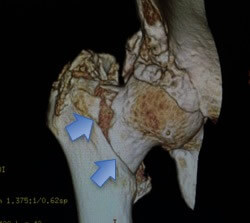

Fig. 1 - Tomografia de Fratura Trocantérica